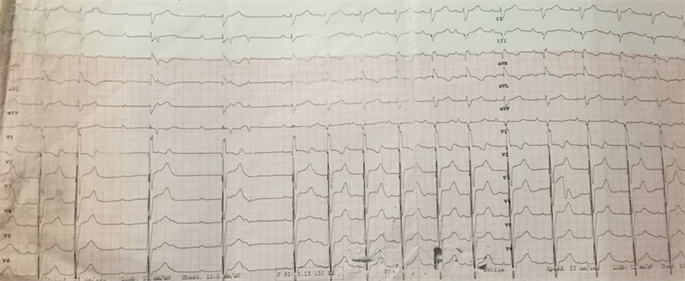

We present a case of 52 year old gentleman, who came to our emergency with complaints of frequent episodes of dizziness for the last 2.5 months. On evaluation he was hemodynamically stable with an unremarkable physical examination except for bradycardia. His 12 lead electrocardiogram revealed a complete heart block with a ventricular escape rhythm of 32 beats/min for which transvenous pacing via femoral vein was instituted (Figure 1). A review of previous medical records revealed the patient to be a known case of coronary artery disease with a history of percutaneous transluminal coronary angioplasty to Left anterior descending coronary artery in 2015. Trans-thoracic echocardiography showed presence of an unruptured sinus of valsalva aneurysm arising from the right coronary sinus invading into the interventricular septum with mild aortic regurgitation and normal left ventricular function. Cardiac computed tomography confirmed the diagnosis of unruptured right sinus of valsalva aneurysm with dimensions of 5 × 2.7 × 5.9 cm. dissecting into the interventricular septum (Figure 2 and Figure 3). Coronary angiogram was also done with showed insignificant stent stenosis of 50% with rest of coronary arteries devoid of any significant stenosis. The patient was taken up for surgical repair via median sternotomy with standard bicaval canulation and cardioplegic arrest. After aortotomy, the right sinus of valsava aneurysm was opened. The aneurysm was dissecting into the interventricular septum. The aneurysmal cavity was filled with mural clots and calcified deposits (Figure 4). The aneurysm was seen distorting the aortic annulus leading to poor coaptation of the aortic valve leaflets. For repair, direct closure of the aneurysm cavity was done and aortic valve was replaced with size 23 mm medtronic ATS mechanical aortic valve (Figure 5 and Figure 6). Patient was weaned of cardiopulmonary bypass normally. Post bypass patient required temporary pacing with epicardial pacing leads. Patient was weaned off ventilator support on day 1 and reverted to sinus rhythm on the same day with a heart rate of 92 beats/min (Figure 7). Patient was finally discharged with sable vitals and uneventful hospital stay. Patient is currently in our bi-annual follow up and symptom free with stable cardiac rhythm.

Figure 1. Electrocardiogram of the patient with and without transvenous pacing.

Figure 7. Post-operative day 3 electrocardiogram showing sinus rhythm.